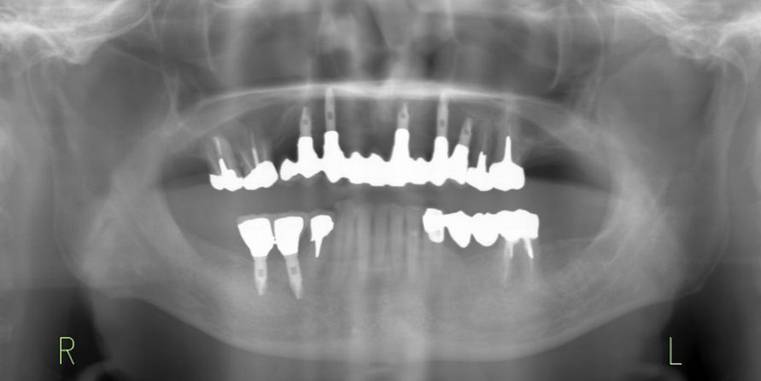

術後。上部構造はハイブリッドレジンです。しっかり嚙めるようになり喜んでいただきました。

上顎

下顎

治療後。歯周病で失われた骨が回復しています。使用インプラントはスプラインツイストです。

上部構造装着後6年。ハイブリッドレジンを使用したため、少し艶がなくなってきました。上部構造の材料には金属、ハイブリッドレジン、セラミックなどがあります。セラミックはきれいですが欠けやすいため、最近はフルジルコニアを使っています。